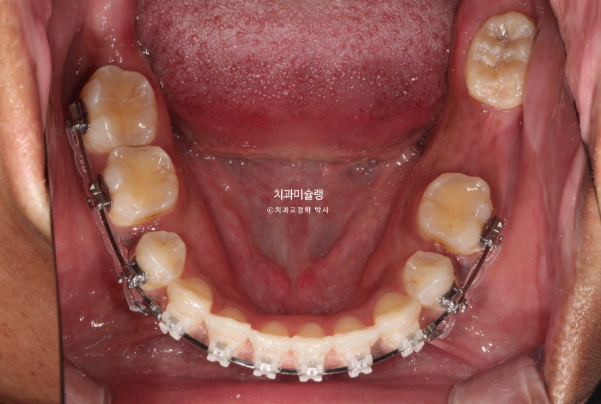

In the mandible, a molar was in a similar condition, with only the root remaining.

For the missing mandibular molar, ideally, the wisdom tooth could be moved forward to replace it. However, the wisdom tooth already showed root inflammation and was not in a healthy condition. Therefore, we decided to extract the wisdom tooth and proceed with orthodontic treatment, followed by implant placement in the molar region.

For the mandibular arch, we decided to extract the second premolar affected by dental caries.

The patient opted for treatment using Clippy-C bracket orthodontics.